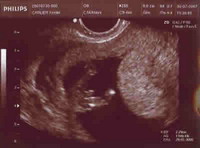

Mes premières photos,

Ma première echographie...

Voici une echo révélatrice...

Le 30/08/2007, je mesurais déjà +/- 15 cm